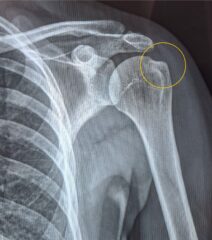

V fizioterapevtsko ambulanto meridian-fit prihaja 44 let stara gospa z bolečino in omejeno gibljivostjo v desni rami. Opravljen je bil tudi RTG slikovno diagnostiko kjer nakazuje na kalcinacijo desne rame. Glede na teste, ki smo jih izvedli v ambulanti in na podlagi slikovne diagnostike smo lažje sestavili plan zdravljenja za našo pacientko.

Po 12 terapiji v meridian-fit je gospa opravila RTG, kateri je pokazal na uspešno zdravljenje kalcinacije v rami. Ob zadnji fizioterapevstki obravi smo izvedli tudi funkcionalno testitanje kjer gospa ni več čutila bolečine.

Po začetnih šestih terapijah je bila funkcionalnost rame izrazito izboljšana. Gibljivost se je približala normalnim vrednostim na primerjavi z nepoškodovano ramo, bolečina pa se je zmanjšala, v mirovanju je skoraj popolnoma izginila. Ob dvigovanju roke se je ohranil le še blag nelagodje. Po devetih terapijah je pacientka začela samostojno izvajati vaje, bolečina ob vsakodnevnih aktivnostih se je znatno zmanjšala, pri določenih gibih, kjer je roka dvignjena nad nivojem glave, je občutila le še rahlo špikanje, ki ni vplivalo na njeno funkcionalnost. Po dvanajstih terapijah je RTG potrdil uspešno zdravljenje kalcinacije, medtem ko je funkcionalno testiranje pokazalo popolno odpravo bolečine. Pacientka je dosegla pomembno izboljšanje kakovosti življenja, saj je lahko normalno izvajala vse dnevne aktivnosti brez omejitev ali bolečin.